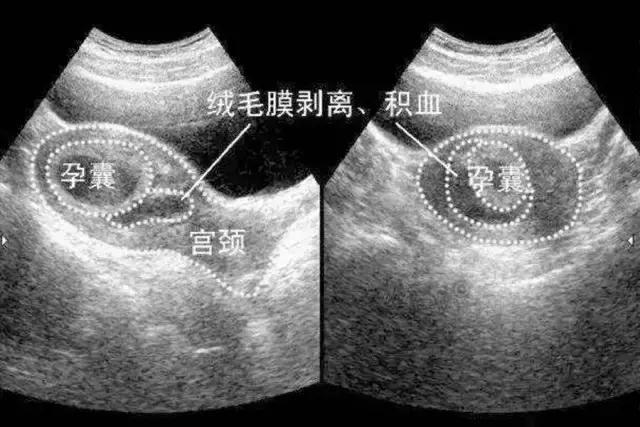

B超报告单上可能会写上这样的字样:低回声或无回声的液性暗区包绕着部分妊娠囊,表面不规则,呈月牙形、三角形或环形,这种字样的报告就是提示我们这个孕妈有绒毛膜下血肿或绒毛膜下出血了。我们医生看到B超单,首先关注绒毛膜下出血的程度,小于孕囊周边的1/3为轻度。达到孕囊周边的1/3—1/2为中度,大于孕囊周边的1/2为重度。

绒毛膜血肿的程度,与自然流产是正相关,也就是说,程度越重,流产的概率越大,大多数的孕妈,在看到B超单有绒毛膜下血肿的提示,会非常紧张。当然,谁都会紧张,除非你不想要这个孩子,但如果血肿是轻度,阴道流血颜色较深,量很少,不用太紧张,注意不要剧烈运动,不能过*生活性**,在医生的指导下服用一些抑制宫缩的药物(比如地屈孕酮),只要阴道流血不增多,颜色没有变成鲜红色没有腹痛,一般问题不大。如果血肿是中度或重度,就一定要重视了,最好住院保胎,因为血肿大了出血多了,绒毛可能会脱离子宫,从子宫壁上滑落下来了,胎盘滑落了,宝宝还能活吗?